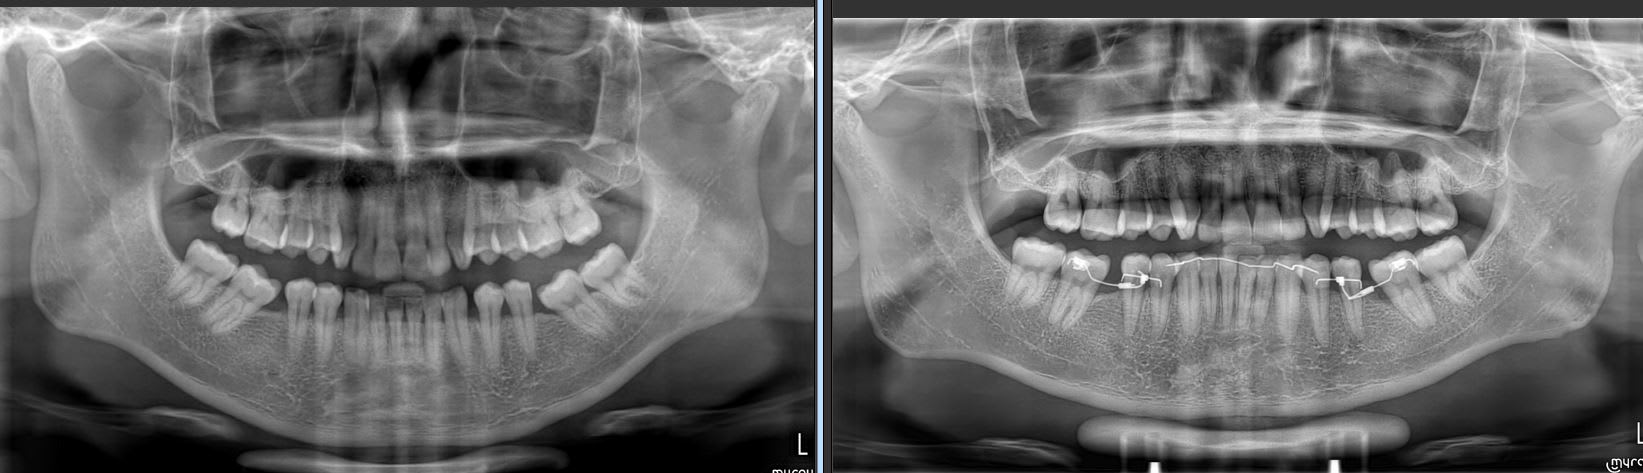

Suivis à 3 mois.

Encore un mois a priori.

Et un autre cas 5 semaines d'interval entre les deux photos.

Enfin là j'ai seulement à ouvrir les espaces pour les implants.